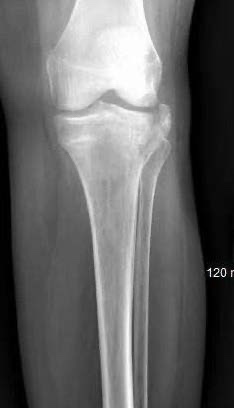

A 63-year-old patient sustained a bicondylar tibial plateau fracture following aground level fall. The patient had an extensive past medical history significant for possible rheumatoid arthritis, hepatitis, CAD, right heart dysfunction, and morbid obesity. CT revealed lateral joint depression and a widening fracture in the metaphysis that indicated significant osteoporosis and medial column instability. Fixation of the medial column was essential to avoiding failure of a lateral only construct; medial wound complications were a significant concern.Following placement of a femoral distractor, the IlluminOss flexible balloon was inserted through the lateral side, running proximal through the intramedullary space to the subcondylar bone medially. The balloon was filled with liquid monomer and cured using visible light. Fixation on the lateral side was achieved using a plate and screw construct. Access through soft tissue on the medial side was avoided completely. At 8-weeks postop the patient was ambulating on the affected extremity with no varus collapse noted.